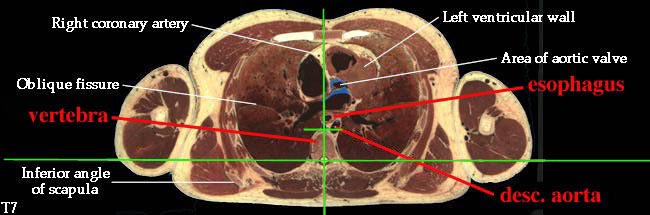

3. Describe the organization of the thoracic sympathetic trunk, in addition to its visceral and splanchnic branches. (W&B 413-416, N158, N160, N165, N209, N240, N254, TG4-45, TG4-46, TG8-03, TG8-14)This set of cross-sections might help (no guarantee!):

- Descending aorta (thoracic portion): the continuation of the arch of the aorta, supplying oxygenated blood to thorax (except the heart), abdomen, pelvic region, and lower extremities. It begins on the left side, but moves to the midline (to lie on vertebrae) as it descends. The branches of the thoracic descending aorta include:

- Esophagus: enters the mediastinum a little to the right of the median plane, posterior to the trachea. It passes to the middle of the body, then to the left and anteriorly as it travels down to the stomach. (See "Extra Explanation" below.)